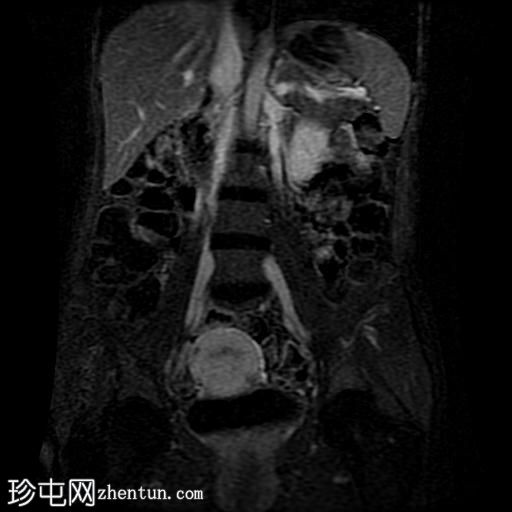

冠状位T2加权像

脂肪抑制

回肠末端及盆腔回肠肠袢可见长段肠壁增厚及强化,肠周血管丰富,呈“梳状征”,并可见明显的纤维脂肪浸润。

未见瘘管、积液、腹水或梗阻。

磁共振肠道造影(MRE)结果支持克罗恩病的诊断,显示远端及末端回肠以活动

性病

变为主,并可见明显的肠周血管。